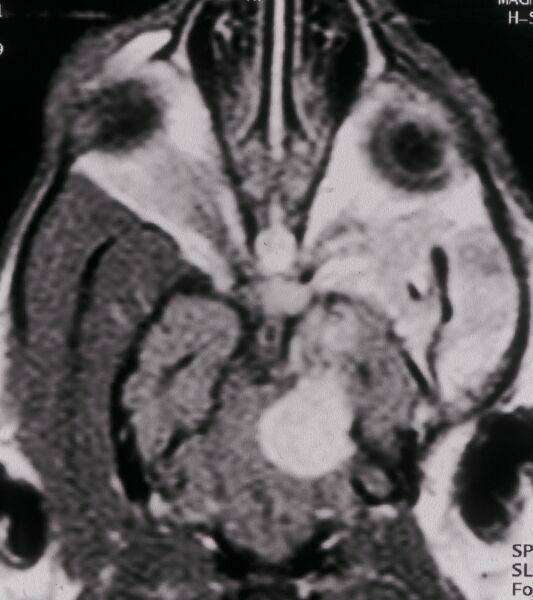

Kernspintomographie Augen-Tierarztpraxis